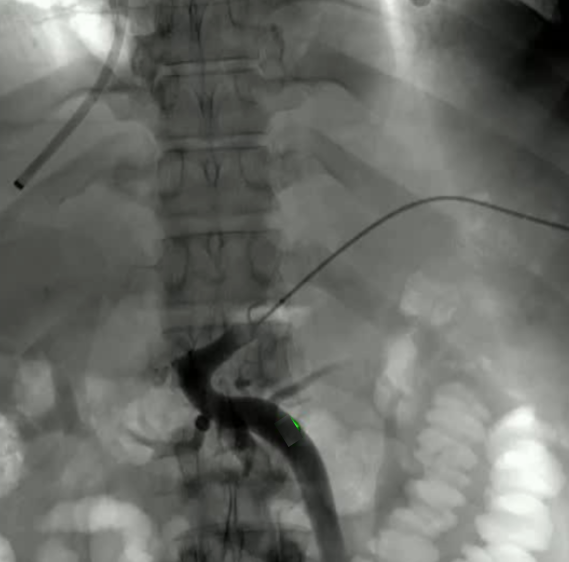

该程序包含以下步骤: 经脾脏入路:在超声引导下,刺穿脾静脉内的一个实质内分支。 在通过脾静脉造影确认了静脉通路后,导管和导丝被推进,以穿过脾静脉并抵达血栓化的门静脉。在门静脉/右门静脉分支处放置圈套器,为TIPS穿刺精准定位。TIPS穿刺圈套器,并穿过圈套器完成TIPS

步骤: 鉴于慢性血栓形成的复杂性: 一种经脾脏途径的门静脉再通术(PVR)。 随后是经颈静脉肝内门体分流术 。

结果:术后影像学检查显示门静脉和脾静脉的血流情况有所改善,且残留血栓极少。